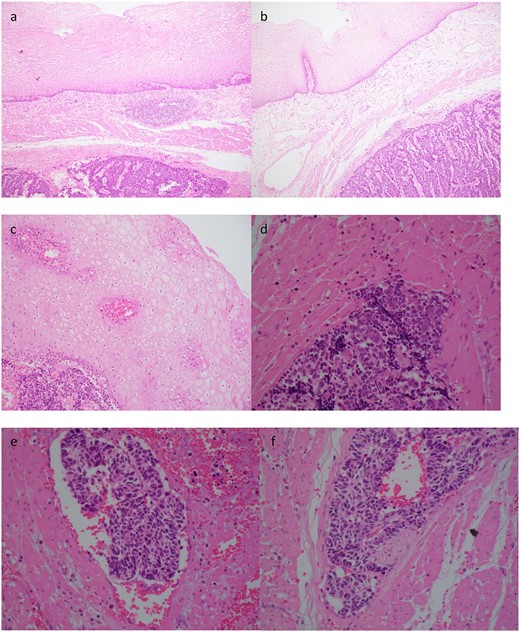

Histopathology demonstrated an SC NEC with pathological stage T2N0. Lymphovascular space invasion was present (Fig. 3). Nine lymph nodes were negative for metastases.

Case 2. Histopathology of the primary tumour. (a) and (b) demonstrates intact overlying oesophageal squamous mucosa, undermined by the infiltrative small cell lesion with invasion of the lamina propria (c), muscularis propria (d), vessels (e) and nerves (f).